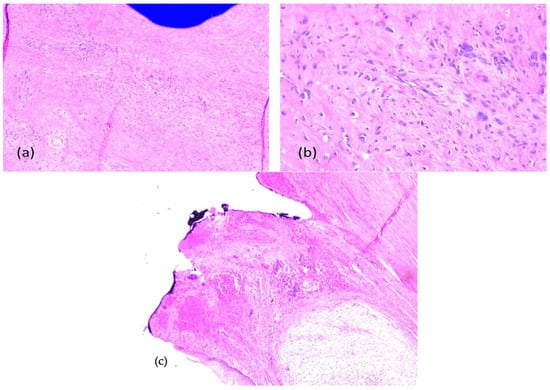

2.3. First Histopathologic Examination

2.4. Second Surgical Intervention